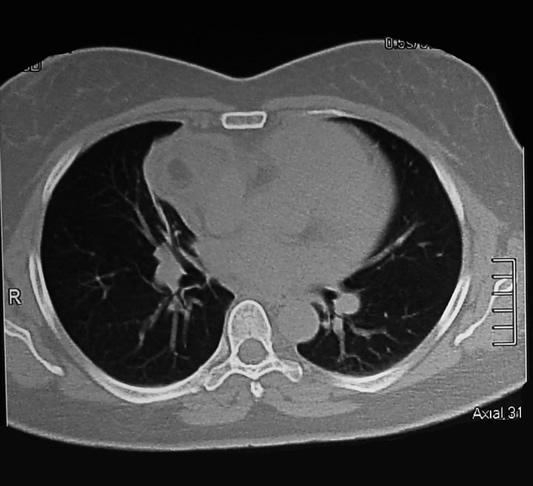

tomografia Corte Axial 31 ventana pulmonar

tomografia Corte Axial 32 ventana pulmonar

Corte Axial en hileo pulmonar

La lesión con forma de pera, encapsulada y densidad heterogénea, su parte mas amplia para cardiaca derecha ocupa el ángulo pleuropericardico anterior y el cuello posterior de la lesión en relación con el seno de la arteria pulmonar y la vena cava superior.

El seno cardiofrenico esta libre y sin derrame pleural.

Corte Axial debajo de los hileos

Un corte axial mas bajo al precedente: la lesión en su mayor diámetro, en relación adosada con la aurícula derecha y el cono aórtico, parece comprimir el parenquima pulmonar ocasionando atelectasia laminar.